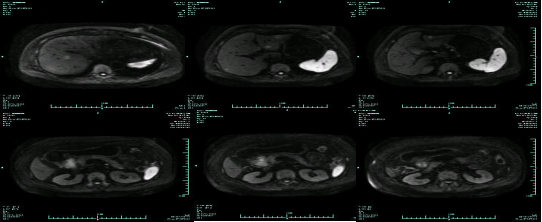

• MR示:

CT-T

CT-H1

MR-H1

影像学检查结果评估:cPD。